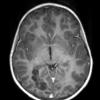

NEOPLASMS (NEURONAL)

DNET (13)